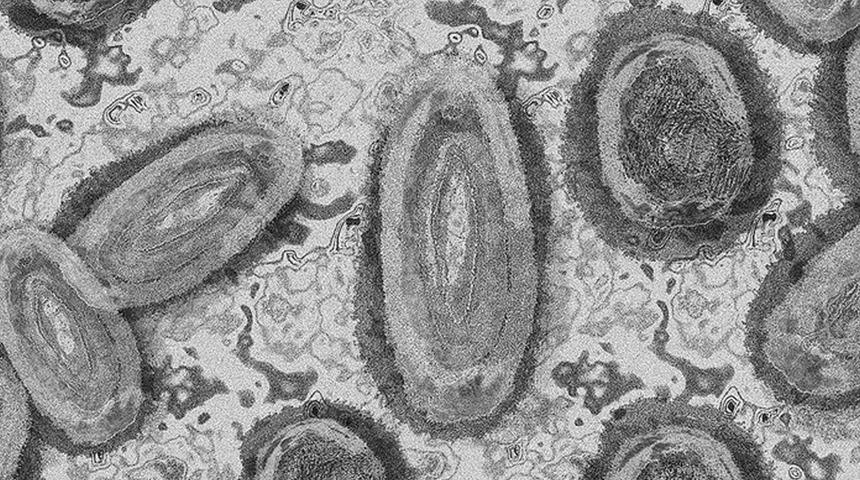

Maymun çiçeği virüsüne karşı dikkat çeken hamle... Aşı stoku yapmaya başladılar!

ABD'den dikkat çeken maymun çiçeği hamlesi geldi. ABD Sağlık ve İnsan Hizmetleri Bakanlığı, maymun çiçeği virüsüne karşı geliştirilen, 36 binden fazla doz aşı siparişi verdi. Öte yandan dünya genelinde şu ana kadar 780 kişide maymun çiçeği virüsü tespit edildi.

Dünyada maymun çiçeği paniği yaşanırken ABD'den çarpıcı bir hamle geldi. Ülkede aşı stoklarının düşüş göstermesi nedeniyle aşı üretimi yapan bir firmadan, 36 binden fazla doz maymun çiçeği aşısı alınacağı bildirildi.

ABD Sağlık ve İnsan Hizmetleri Bakanlığından (HHS) yapılan açıklamada, Bavarian Nordic şirketine 36 binden fazla doz aşı siparişi verildi.

Dünya Sağlık Örgütü (DSÖ), son haftalarda dünyada yayılmayı sürdüren maymun çiçeği virüsünün şimdiye kadar 780 kişide tespit edildiğini duyurdu.

İngiltere'de 270, İspanya'da 156, Portekiz'de 138, Kanada'da 58, Almanya'da 57, Fransa'da 33 ve Hollanda'da 31 vakanın tespit edildiği aktarıldı. (Reuters-AA)